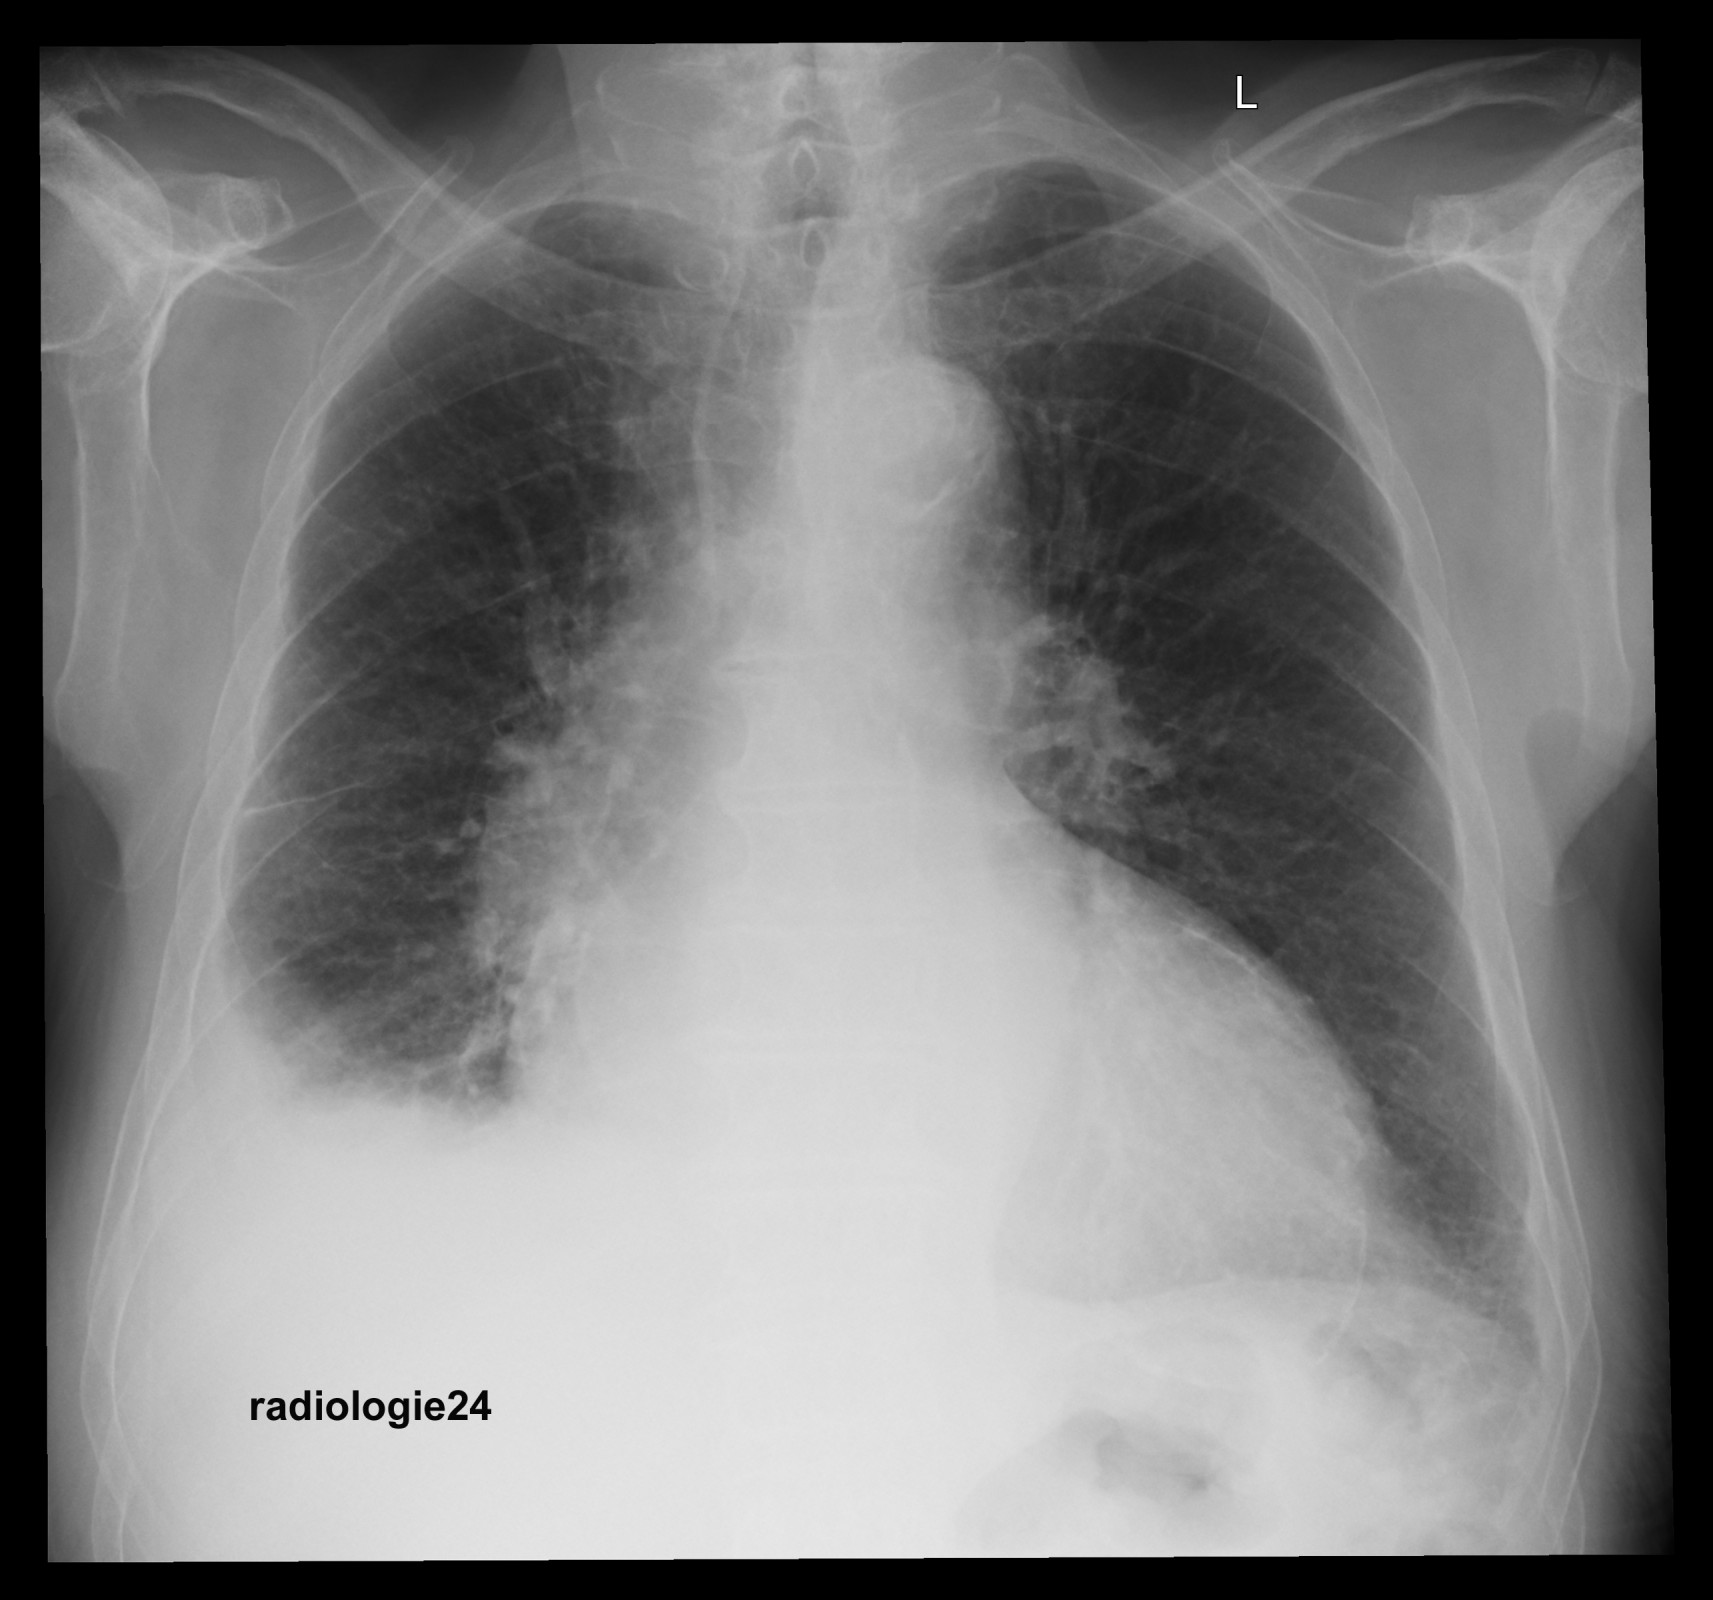

Röntgenfall des Monats Februar 2018 mit Auflösung

75 jähriger Patient

Zunehmende Belastungsdyspnoe.

Ihre Diagnose? Nebenbefunde?